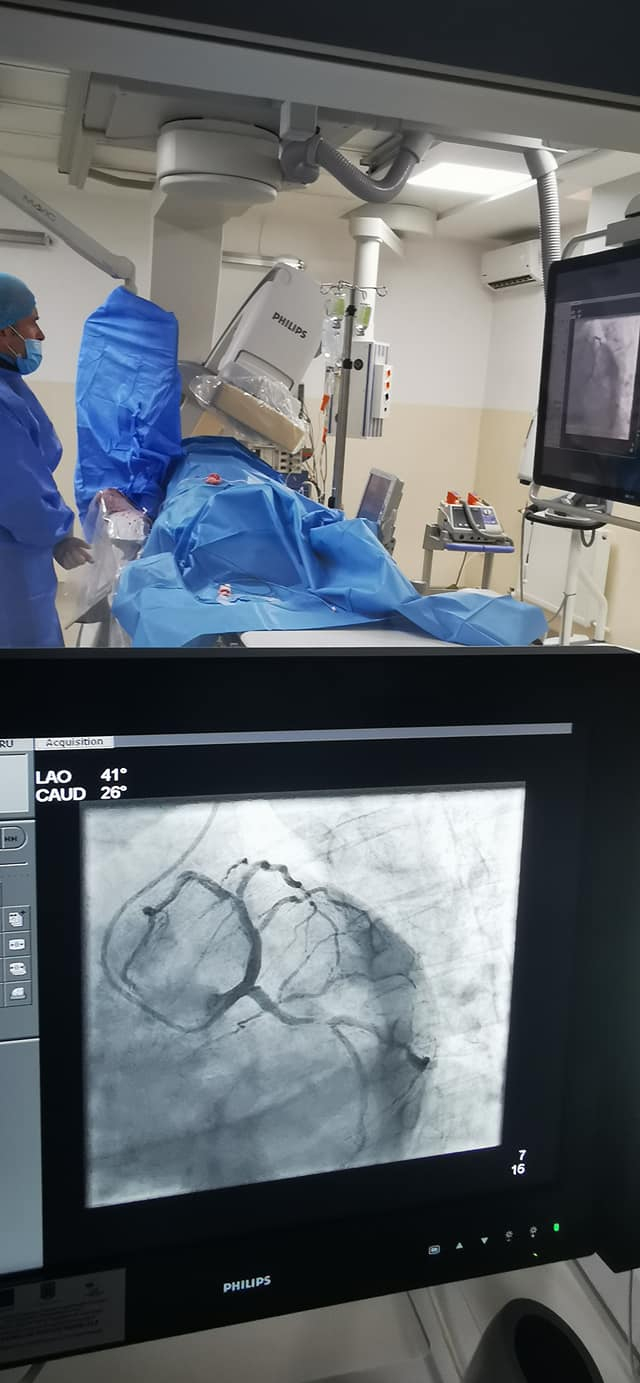

În acest sens, bugetul total al proiectului ar urma să ajungă la 3.226.342,79 lei inclusiv TVA, din care valoarea totală eligibilă este 1.737.190,03 lei. În mod similar, ca urmare a scumpirilor din ultima vreme, şi lucrările nestructurale şi de instalaţii aferente Secţiei de Cardiologie Intervenţională din cadrul Spitalului Clinic Judeţean de Urgenţă „Sf. Apostol Andrei” se preconizează a fi suplimentate până la o valoare totală a investiţiei de 2.419.006,29 lei inclusiv TVA, din care C+M (construcţii-montaj) 2.089.977,17 lei. La începutul acestui an, valoarea proiectului era estimată cu circa 600.000 de lei mai puţin.